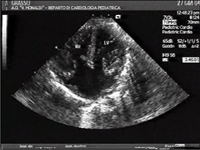

AVSDs can be detected by cardiac auscultation; they cause atypical murmurs and loud heart tones.[7] Confirmation of findings from cardiac auscultation can be obtained with a cardiac ultrasound (echocardiography - less invasive) and cardiac catheterization (more invasive).

Tentative diagnosis can also be made in utero via fetal echocardiogram. An AVSD diagnosis made before birth is a marker for Down syndrome, although other signs and further testing are required before any definitive confirmation of either can be made.